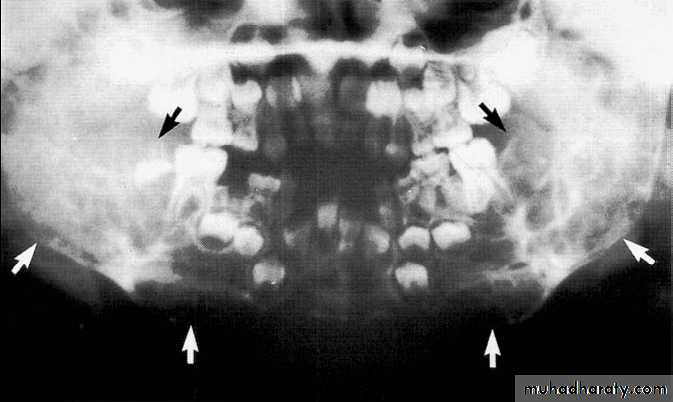

• Cherubism

*Hereditary & involve many members of the family.*Age; <20 years.

*Affect the jaw bone only.

*Bilateral, expansile, multiple, soap bubble-like radiolucencies in the mandible.

*Migration of teeth & tooth germ, without exfoliation or become loosed.

5-year-old boy showing the typical bilateral multilocular lesions of

cherubism affecting the mandible (arrowed).Multiple but separate radiolucent lesions